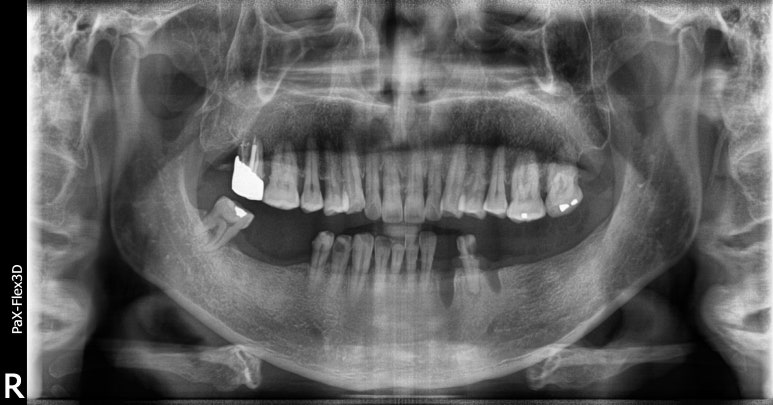

임플란트건강보험 시술 전 엑스레이 사진

2021-11-05

환자분 시술 전 모습을 보시면 하악쪽 어금니 상당수를 상실하신 상태로 내원해주신 것을 확인하실 수 있는데요.

이대로 계속 방치하게 되면 우선 음식을 씹는데 문제가 많이 생기기 때문에 소화불량, 위장질환 등 다른 질병까지 불러올 수 있고

맞닿는 치아가 없는 상악쪽 치아들이 아래로 내려와 결국에는 윗니까지 문제가 발생할 수 있습니다.

따라서 우선 아직 잇몸뼈의 양이 남아있는 오른쪽 아래 어금니(사진상 왼쪽 아래)는 임플란트건강보험 적용을 받기로 하고

왼쪽 아래 어금니(사진상 오른쪽 아래)는 일반적인 임플란트 식립을 진행해 상실된 치아를 대체하기로 했습니다.